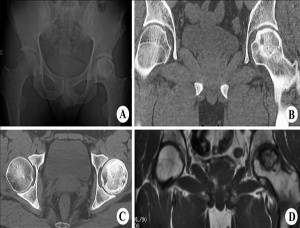

股骨頭壞死是由于不同病因破壞了股骨頭的血液供應,造成血供障礙,因缺血使骨組織營養中斷、骨細胞死亡,以不定區域的骨小梁和骨髓壞死為特征的骨科常見病。

股骨頭壞死分期及療效

I期:無或隱痛 ;股骨頭外觀正常,軟骨、骨小梁結構稍模糊,或呈斑點狀骨質疏松,可見輕度密度增高區或減低區,甚至可以陰性。可以治愈。

II期: 疼痛不適,活動勞累后加重,休息后減輕、可有跛行。骨質密度正常或有明顯斑點狀密度增高,頭無塌陷,有分界明顯的骨硬化區。可以治愈。

III期:疼痛明顯、跛行;軟骨下骨折,出現"新月癥"或扇形骨折 ;可以治愈。

IV期:跛行嚴重、出現功能障礙;全頭或大面積塌陷,股骨頭扁平,關節間隙變窄 ,可臨床治愈

V期 :功能明顯障礙;股骨頭變形、死骨碎裂、關節間隙明顯變窄。可見片狀密度增高影。可維護關節基本功能。

VI期:功能嚴重障礙;股骨頭肥大、變形、脫位、關節間隙完全消失、髖臼不光滑甚至硬化增生;建議行關節置換術配合藥物治療。